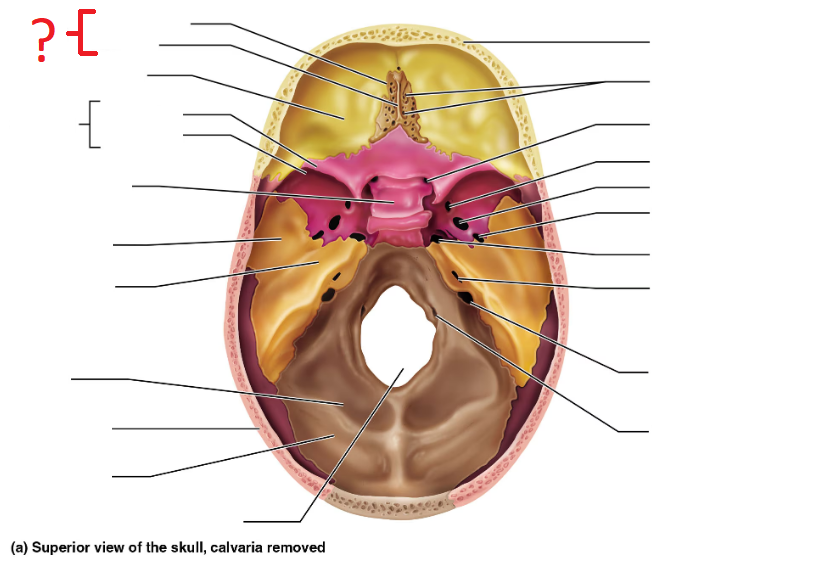

Ethmoid bone

Crista galli

Cribriform plate

Greater sphenoid wing

Lesser sphenoid wing

Sella turcica, protects pituitary gland

Foramen magnum (superior interior view)